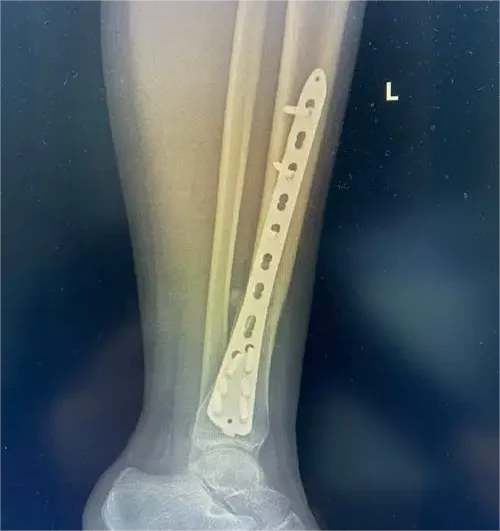

手术治疗包括内固定和外固定。内固定常用的手术方式有髓内钉固定和钢板内固定,根据骨折的具体情况选择适合的手术方案。此外,对于开放性骨折还需进行清创,预防感染。